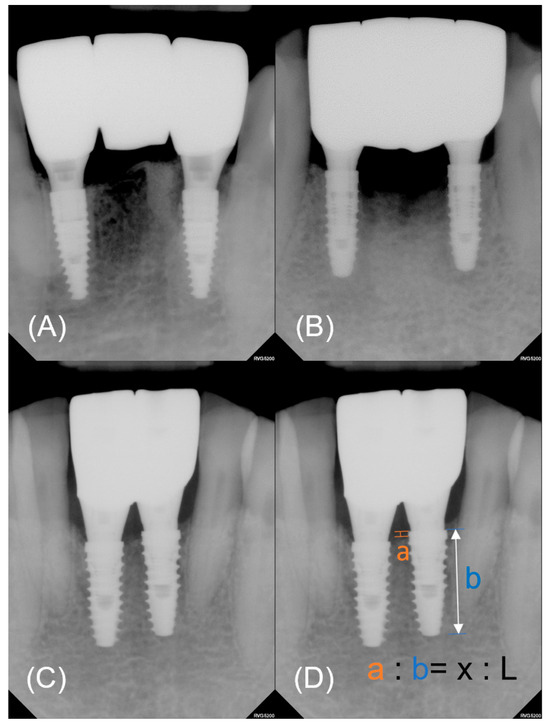

2.3.4. Marginal Bone Loss Evaluation